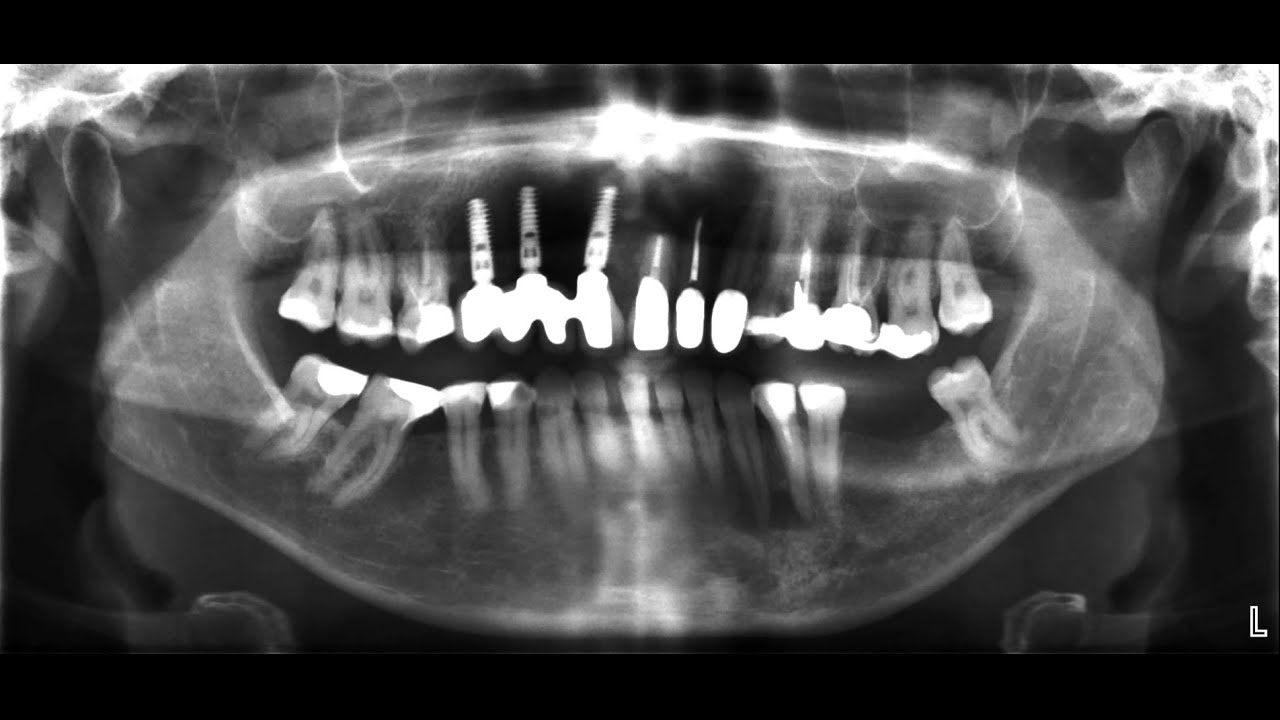

für Zahnärzte: das OPTG Röntgen

Описание: im medizinstudium lernt man nicht das, was man für die praxis braucht - röntgenanalysen wurden bei uns nur gestreift, obwohl das röntgen ein sehr wichtiges diagnostisches tool ist. mit dem panormaröntgen kann man viele informationen gewinnen und das nicht nur über die zähne. man kann aussagen über die nasennebenhöhlen, die kiefer, den hals, das kiefergelenk und die parotis bekommen.